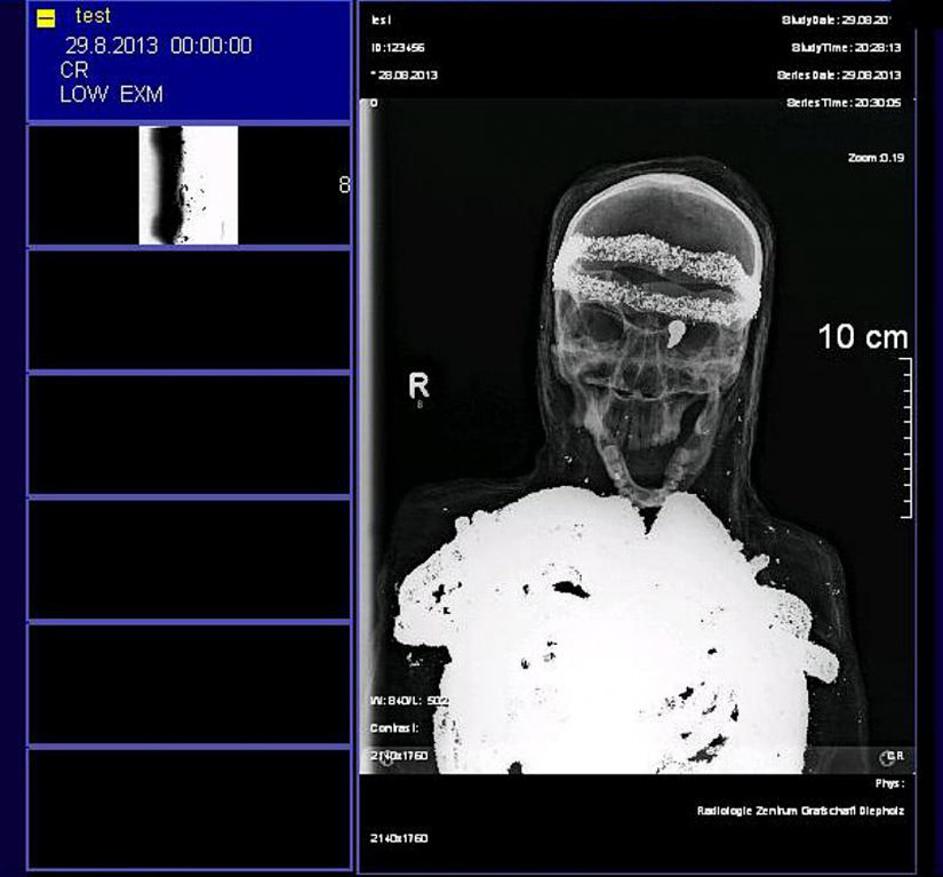

Mumija v Nemčiji To je mumija, ki jo je deček našel pozabljeno na dedkovem podstrešju. EPA Mumija v Nemčiji

Mumija v Nemčiji Mumija v Nemčiji EPA Mumija v Nemčiji